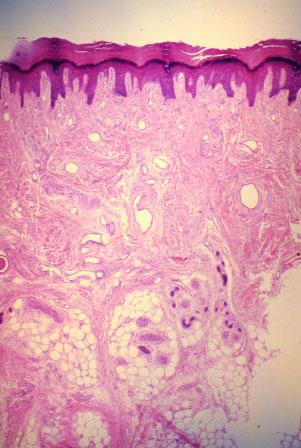

III-15 (4) Slide 79, Thick Skin. Low power view of epidermis (top, dark staining area), dermis (dense irregular connective tissue), and hypodermis (adipose tissue).